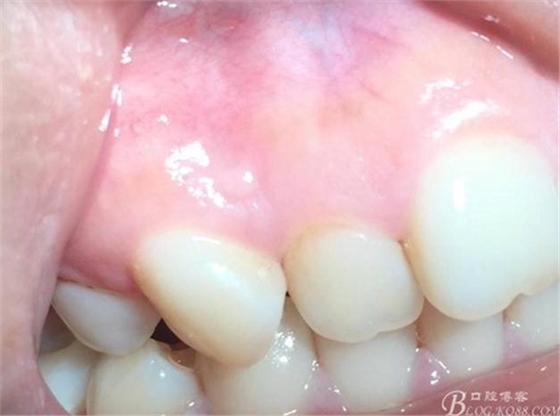

術(shù)后24小時(shí)

術(shù)后3日